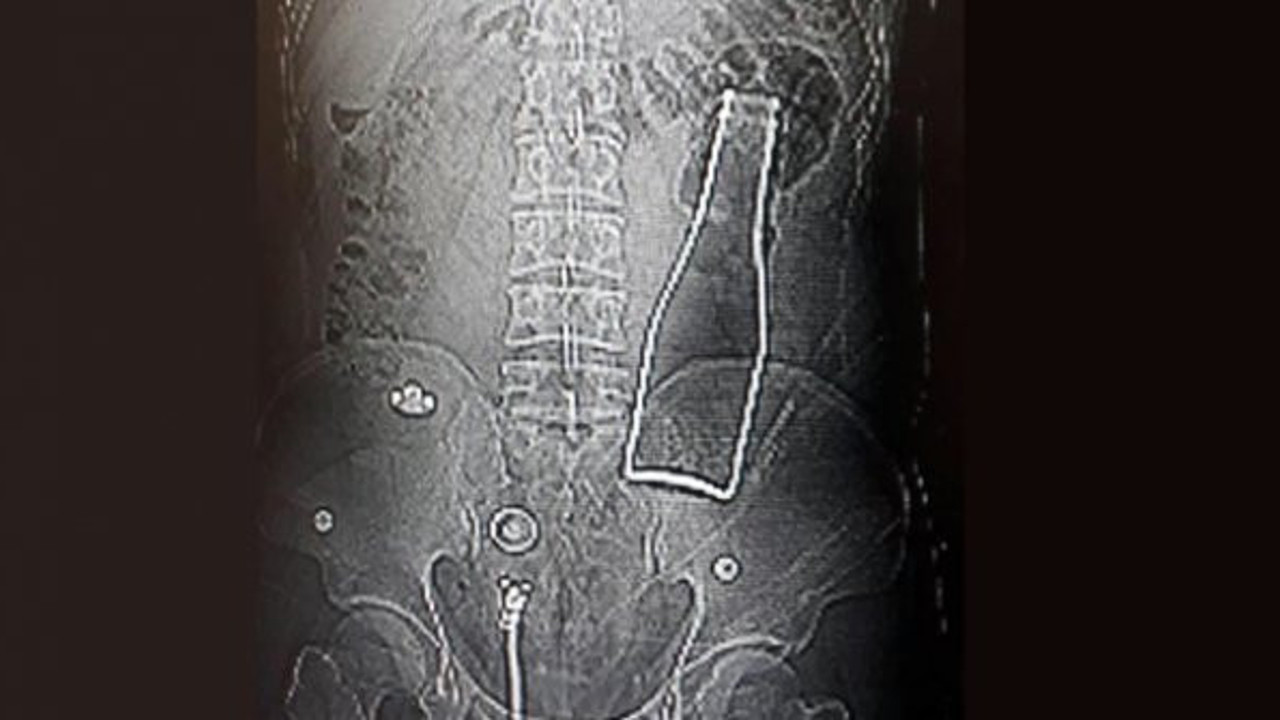

Karaman'da karın ağrısı ile doktora giden bir kişinin röntgen sonuçları akıllara durgunluk veren cinstendi. Afgan uyruklu olduğu belirtilen 27 yaşındaki kişinin kalın bağırsağında şişe olduğu ortaya çıktı.

KaramanEğitim ve Araştırma Hastanesi'ne gelen A.E., doktorlara karın ağrısı şikayetinin olduğunu söyledi. Çekilen röntgen filminde A.E.'nin kalın bağırsağının bulunduğu bölgedeşişeolduğu tespit edildi. A.E.'nin makatından sokulduğu belirlenensodaşişesi, yaklaşık 1 saat süren ameliyatla çıkarıldı.